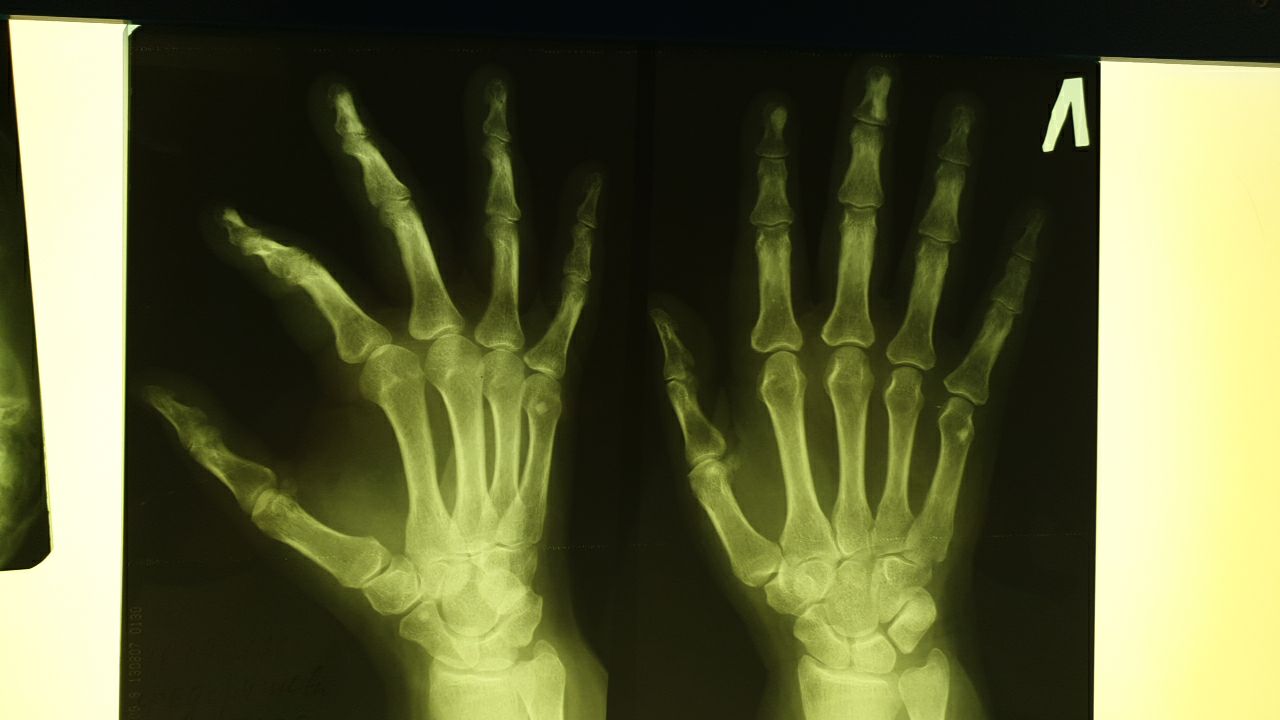

Сурхо in Radiology/Рентгенология Чатоид

Приветствую коллеги! Ж. Жалобы на гигрому. В дистальных фалангах мелориостоз?